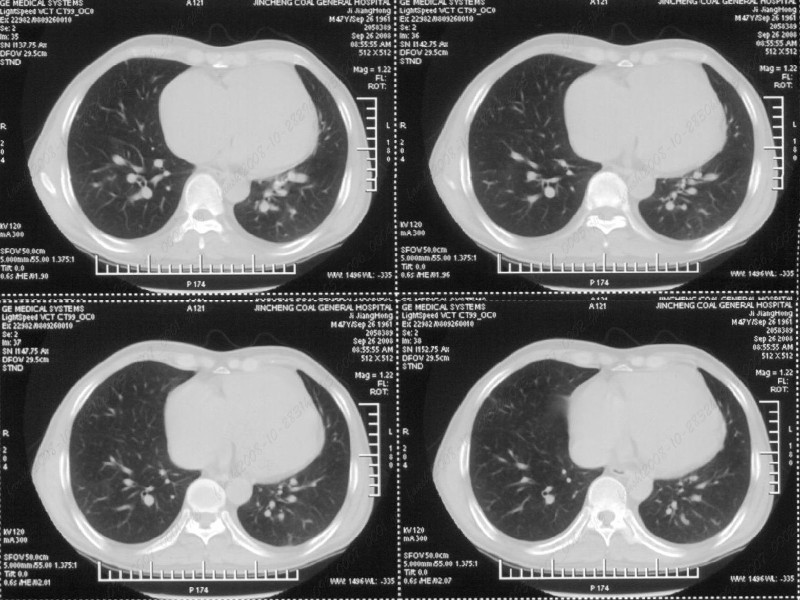

男性,47岁。胸部不适一年,ct检查发现右胸膜下结节。http://www.radida.com/bbs/forum.php?mod=viewthread&tid=46094

图像很清,资料很全。工作做的很细,向您学习!观阁下的强化图像发现,您们强化后扫描时间挺早,延迟时间大约在16—18秒之间吧。估计目的是为了观察肺动脉及分支的情况。但现有的资料并不能提示动脉栓塞改变。建议楼主可在机器上仔细观察,或许会有异常发现。另外,个人感觉右侧应为肺内结节而非胸膜结节。考虑肺内良性小结节,炎性假瘤可能性大。

右下肺前胸膜下小结节,强化不明显。建议定期观察!

病灶周围似有纤维化征像,增强明显强化,但中央可见点状低强化区,考虑慢性病变可能如炎性假瘤等,病灶边缘部分毛糙有切迹,双侧胸腔少量积液影,不除外恶性

结节未见明显强化,局部胸膜增后粘连,内缘纹理影增重伴小围星灶,局部胸膜下小三角状实变影,尖端见纤维索牵扯征,综合考虑炎性病变,有增殖表现,不出外tb灶

右肺中叶外侧段胸膜下结节状病灶,性质待定(不排除周围型肺癌可能)。

右前胸膜下小结节,边缘有小纤维条索影与胸膜粘连,考虑如炎性假瘤之类慢性病变可能。期待二周后的结果。

小结节的周围似乎与斜裂的走行有关,边缘分界不很清楚,与侧胸膜关系密切,有轻度强化,不能除外恶性,建议密切观察。

右下肺胸膜下小结节,强化不明显。建议定期观察!